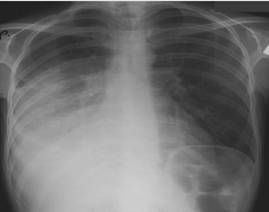

$$$003

Науқас 28 жаста, 1,5 жұма бұрын дене температурасы 38,6 С дейін көтеріліп жіті ауырып қалды, құрғақ жөтел, дем алғанда кеуде жасушасының сол жақ бөлігінде қатты ауырсыну бар. Кеуде қуысы ағзалары рентгенограммасында жоғарғы қисық контурымен сол жақ өкпе шеттеріне дейін, гомогенді субтотальды қарайған анықталды, көкірек мүшелері оңға ығыстырылған.

Қандай патология нақты рентгенологиялық синдромда көрсетіледі:

{Дұрыс жауабы} = C